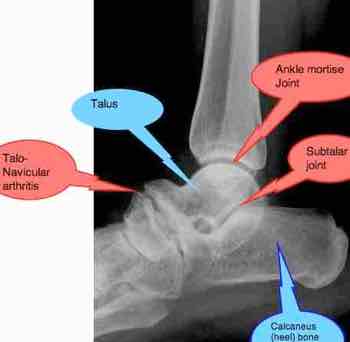

This is the joint that causes needle-sharp pain when you try to walk on a sprained ankle. The subluxated talus is probably the easiest for your chiropractor to reduce after you have injured your leg.

This complex known generally as the subtalar joint too may be subluxated in the ordinary inversion ankle sprain. If it's not reduced after injury, it often causes foot pain in the future.

Actually, it's really three joints, in itself.